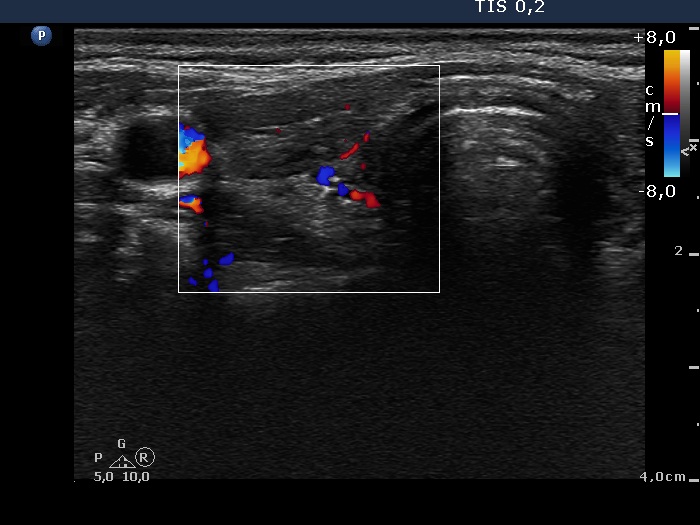

First examination (first row):

Clinical presentation: a 17-year-old girl who has been treated for hyperthyroidism for 2 years. She had no complaints.

Palpation: no abnormality.

Functional state: euthyroidism on daily 10 mg methimazole with TSH 2.14 mIU/L, FT4 13.2 pM/L.

Ultrasonography: the thyroid was echonormal with a hyperechogenic lesion in the central part of the right lobe. The vascularization was a little bit increased.Suggestion: discontinuation of thyrostatic therapy and follow-up examination 6 months later.